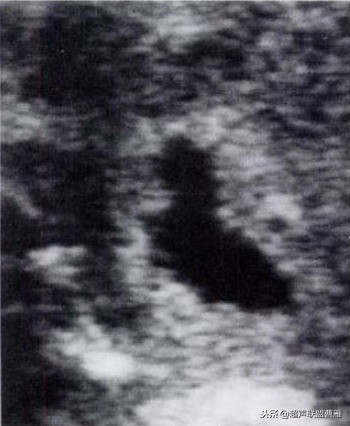

变形的妊娠囊,多系死胎

小孕囊虽有胎体预后不良;妊娠囊平均值减去胎体臀长不应小于5mm。